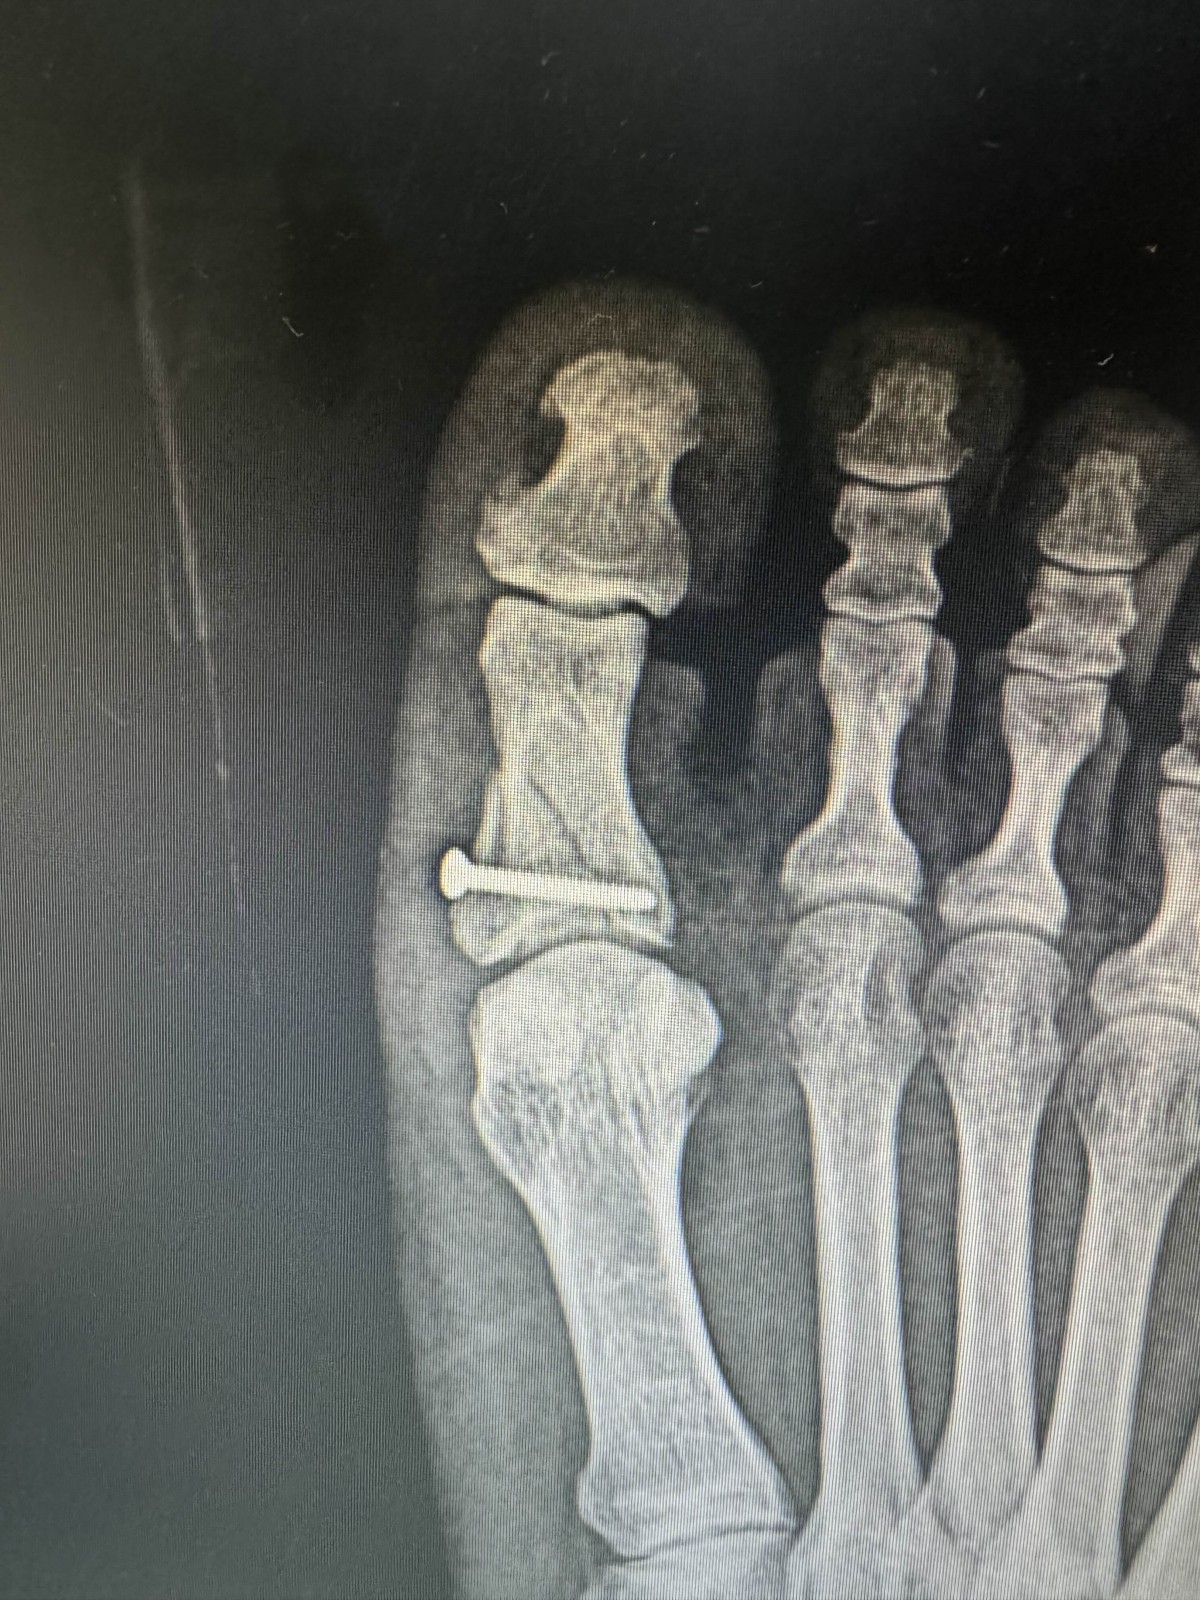

남자 35세, 엄지발가락 골절으로 수술받은 후 2주차 경과 xray입니다.

xray상 으로는 뼈조각이 약간 돌아가서 떠있고 관절면에서 step-off이 보이니, 미래를 봤을때 관절염이 올수도 있다.  아직 확실치는 않지만 재수술을 고려해 보는것도 좋겠다는 소견을 받았습니다.

물론 xray 두장으로만으로 판단하기 불가능하겠지만, 괜찮으니 기다리면 되는 상황인지, 혹시 재진료와 재수술 고려가 필요한 상태인지,  원장님께서 귀중한 소견을 주시면 감사하겠습니다. 또한 재수술을 한다면 가능한지, 언제 하는게 좋은지도 알려주시면 감사하겠습니다.